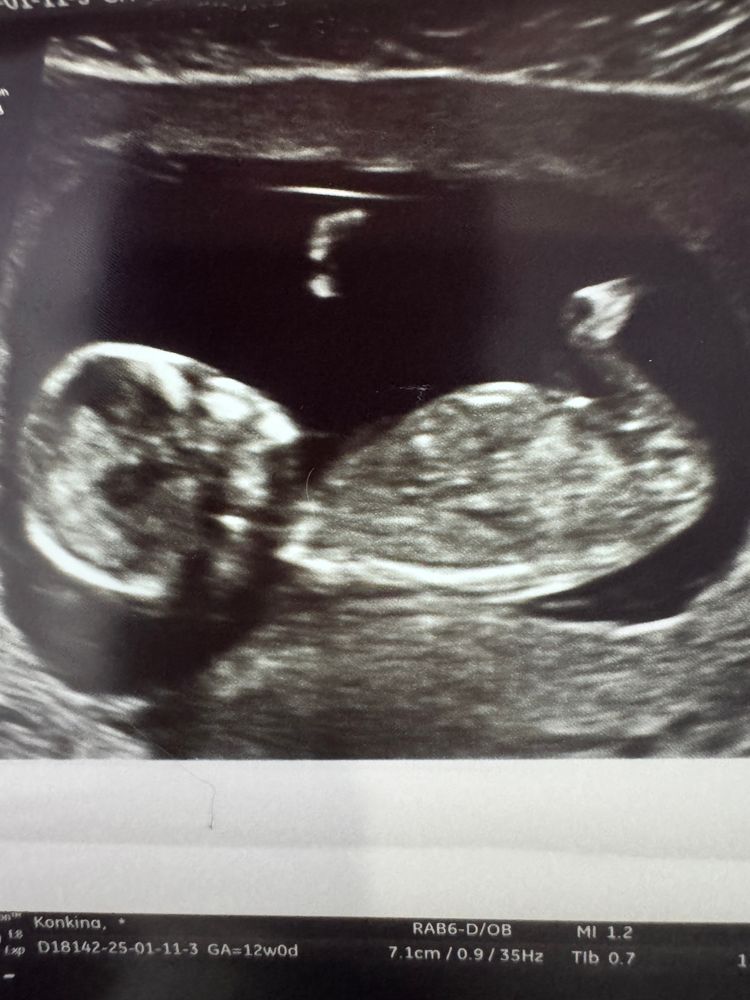

Пол по половому бугорку

Девочки, помогите пожалуйста❤️🙏 13 недель, сходила на узи. Видно тут половой бугорок и возможно предположить пол малыша?! Дурная беременная голова не дает мне покоя😂

P.S. Дополняю) сходила на узи в 16,5 недель подтвердили девочку 🌸